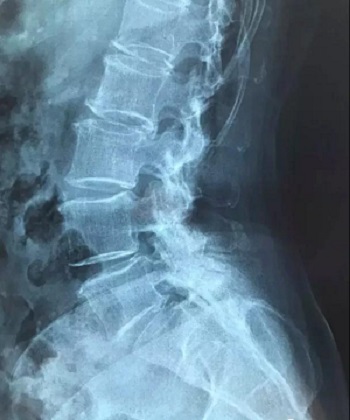

十三、CT片子的翻拍,请参考磁共振片子的翻拍,道理是一样的,先拍一张整图,然后再分区域进行拍摄。